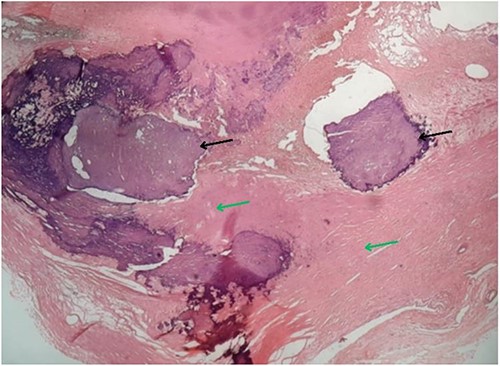

Based on the clinical evaluation, we made a provisional diagnosis of calcified right atrial myxoma extending up to the IVC. We planned for surgical resection of the tumour. We cannulated the right femoral vein and superior vena cava. Then, we did a cardiopulmonary bypass via aortic cannulation followed by a right atriotomy. Standard cardiopulmonary bypass was used during the procedure. The IVC was cannulated with extreme care. We kept the patient in the Trendelenburg position with a venous cannula (32Fr) to ease the introduction of the bulk away from the IVC orifice and away from the cannula. To make the mass easier to remove and prevent fragmentation, entrapping of the IVC was avoided. To better expose the IVC opening, we underwent a right atriotomy in the shape of a T. A solid, spherical, reddish-white lump of 1.8 × 1.8 cm2 in size was found with a broad base linked to the right atrium’s anterior superior IVC junction. The entire mass was removed, and its base was cauterized. The mass was hard, calcified, attached to the right atrium, and extended into IVC. A gross morphology examination revealed a single irregular greyish-white piece of tissue measuring (4.2 × 3.3 × 2.5) cm3 and weighing 15 g (Fig. 3). Microscopy revealed multiple fragments of extensively calcified fibrous lesions with focally abundant myxoid stroma with stellate cells, necrosis mitotic activity, atypia and pleomorphism were absent, which confirmed the diagnosis of calcified atrial myxoma (Fig. 4). The postoperative course was unremarkable, and the patient reported symptomatic improvement in the follow-up visit after one month of operation. During the postoperative follow-up, it was noted that the patient had normal vitals and no signs of infection. The preoperative symptoms of shortness of breath and chest heaviness had been entirely resolved. The patient was able to resume daily activities without any difficulty. The ECG and other cardiac tests revealed no abnormal findings, indicating the patient’s heart function had been restored to normal.

Microscopy of the resected specimen showing focal calcified (black arrow) and myxoid areas.